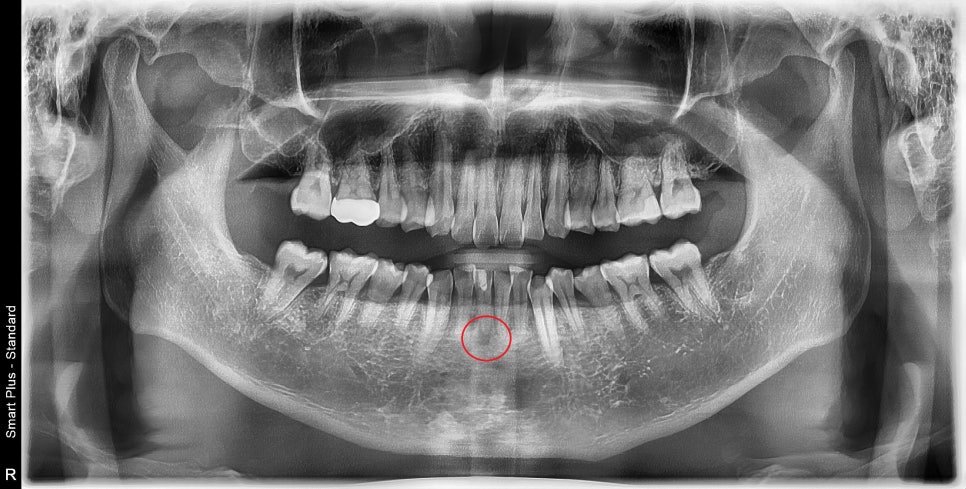

엑스레이 사진상에서 아래 앞니 뿌리 끝이 염증이 생긴 것을 확인할 수 있었습니다.

신경치료가 중단된 상태로 보이고, 치아 주변의 수복물은 오래되어 누출이 일어났을 것이고

주변 잇몸도 치석으로 인해 관리가 필요한 상태였습니다.